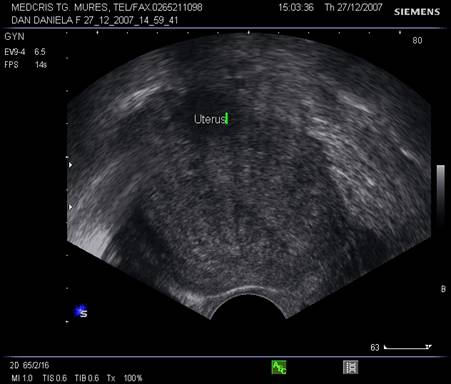

Uterul - situat intre vezica si rect, pozitia lui poate fi variabila, influentata si de umplerea vezici. De obicei, corpul uterin si colul au o relativa omogenitate interna ecografica. Cateodata imagini anecogene in peretele cervical reprezinta chiste Naboth.

Vasele uterine apar in 1/3 externa a miometrului, cu contur neregulat, anecogene si usor de recunoscut la Doppler.